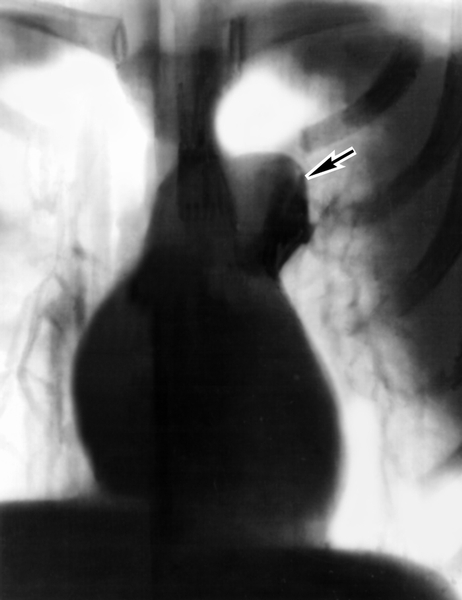

Рентгеновские снимки тератомы средостения: Диагностика и лечение

Раздел: Фотоэссе